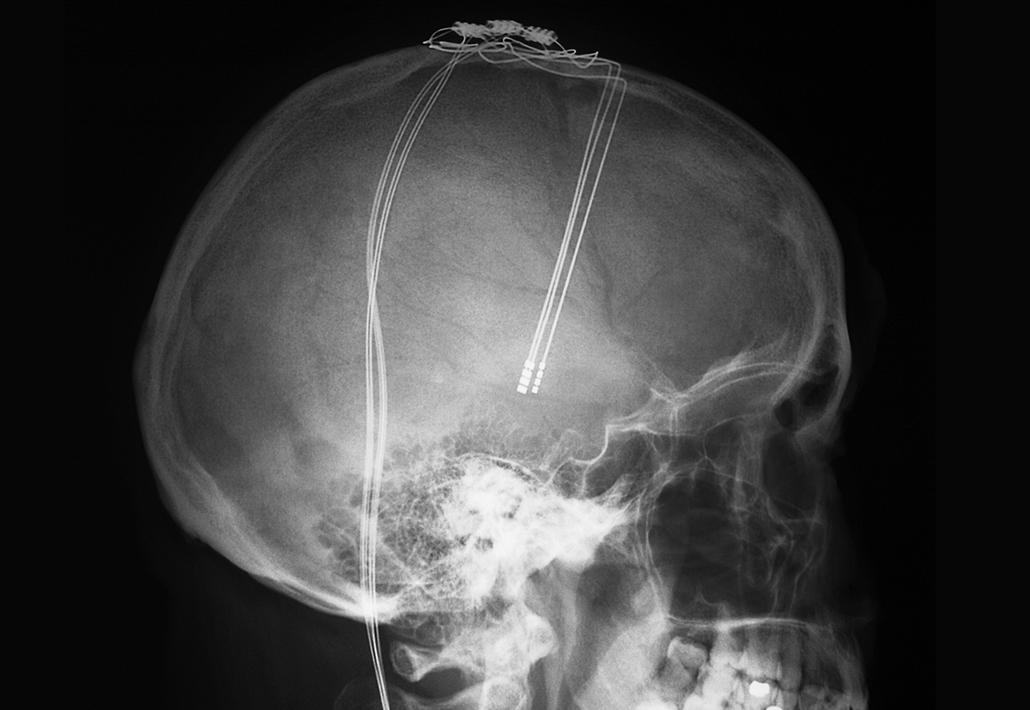

Already, a technique known as deep brain stimulation, or DBS, uses electrodes surgically implanted in people’s brains to tweak the behavior of brain cells. Such electrode implants are helping reduce Parkinson’s tremors, epileptic seizures and uncontrollable movements caused by Tourette’s syndrome. Mood disorders like Sarah’s have been targeted, too.

The central idea of DBS — that the brain can be fixed by stimulating it — is not new. In the 1930s, psychiatrists discovered that a massive wallop of seizure-inducing electricity could sometimes relieve psychiatric symptoms. In the 1940s and 1950s, researchers studied whether more constrained electrical stimulation could help with disorders such as depression.

In 1948, for instance, neurosurgeon Lawrence Pool of Columbia University’s Neurological Institute of New York implanted electrodes to stimulate the brain of a woman with severe Parkinson’s who had become depressed and lost weight. Soon, she began to “eat well, put on weight and react in a more cheerful manner,” Pool reported in 1954. The experiment ended three years later when one of the wires broke. “It is the writer’s conviction that focal controlled stimulation of the human brain is a new technique in psychosurgery that is here to stay,” Pool wrote.

Over the last several decades, researchers have grown ever more precise in their abilities to effectively change brain activity. Companies such as Medtronic, St. Jude Medical (now Abbott), Boston Scientific and NeuroPace have developed new electrodes and new algorithms to make electrical stimulation more effective, providing a clinical option for people with epilepsy, tremors and Parkinson’s disease who cannot be helped by other treatments.

Approaches other than implanted electrodes are showing promise, too. Powerful magnetic fields, ultrasounds and even external electrodes can change brain activity from outside the skull, all with varying amounts of precision and power.

Compared with those early days, today’s scientists understand a lot more about how to selectively influence brain activity. But before a treatment such as Sarah’s is possible, two major challenges must be addressed: Doctors need better tools — nimble and powerful systems that are durable enough to work consistently inside the brain for years — and they need to know where in the brain to target the treatment — a location that differs among disorders, and even among people. These are big problems, but the various pieces needed for this sort of precision healing of the brain are beginning to coalesce.